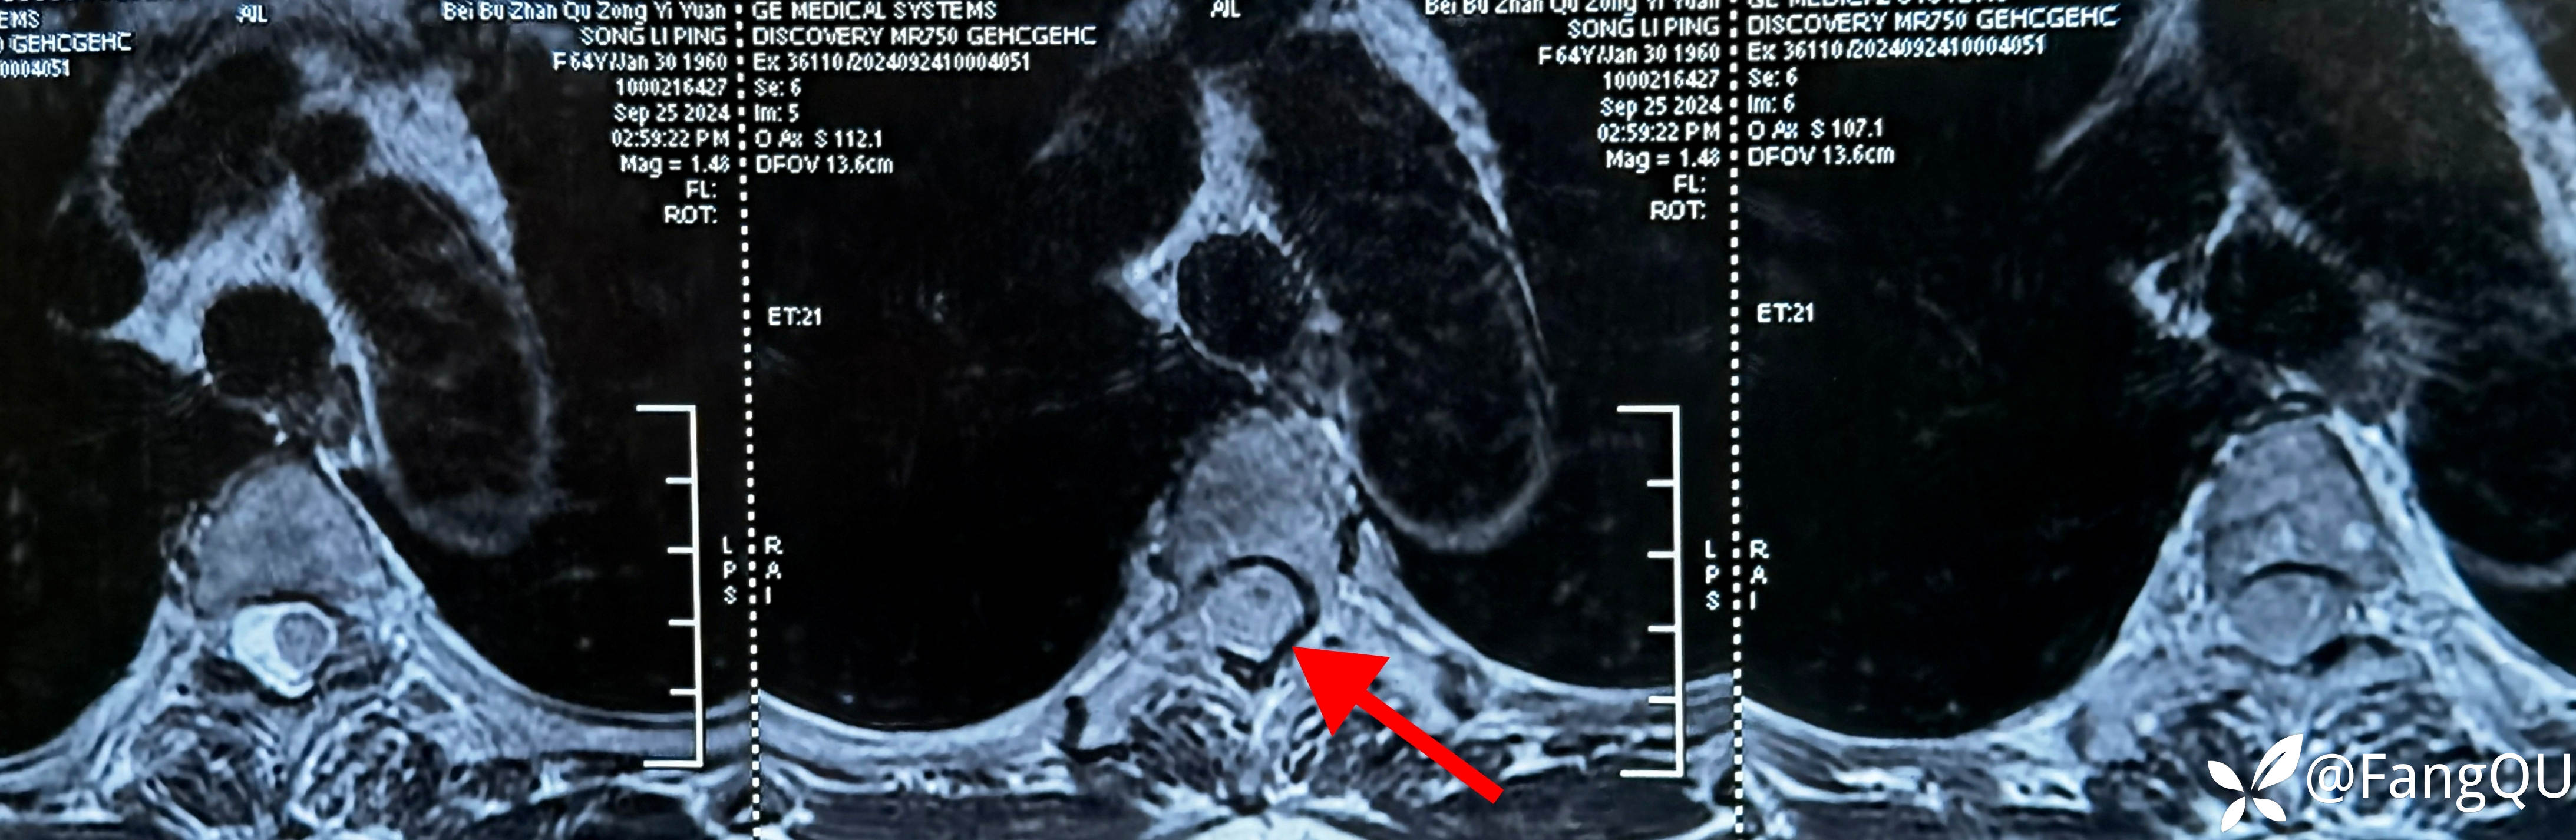

片子出来后家属复诊时说,这次终于找到病根啦,看到“占位”的字样没敢让病人知道也没敢带病人来门诊,胸椎MRI相当胸3节段脊髓信号异常,考虑髓外硬膜下病变?当然转给神经外科兄弟啦!